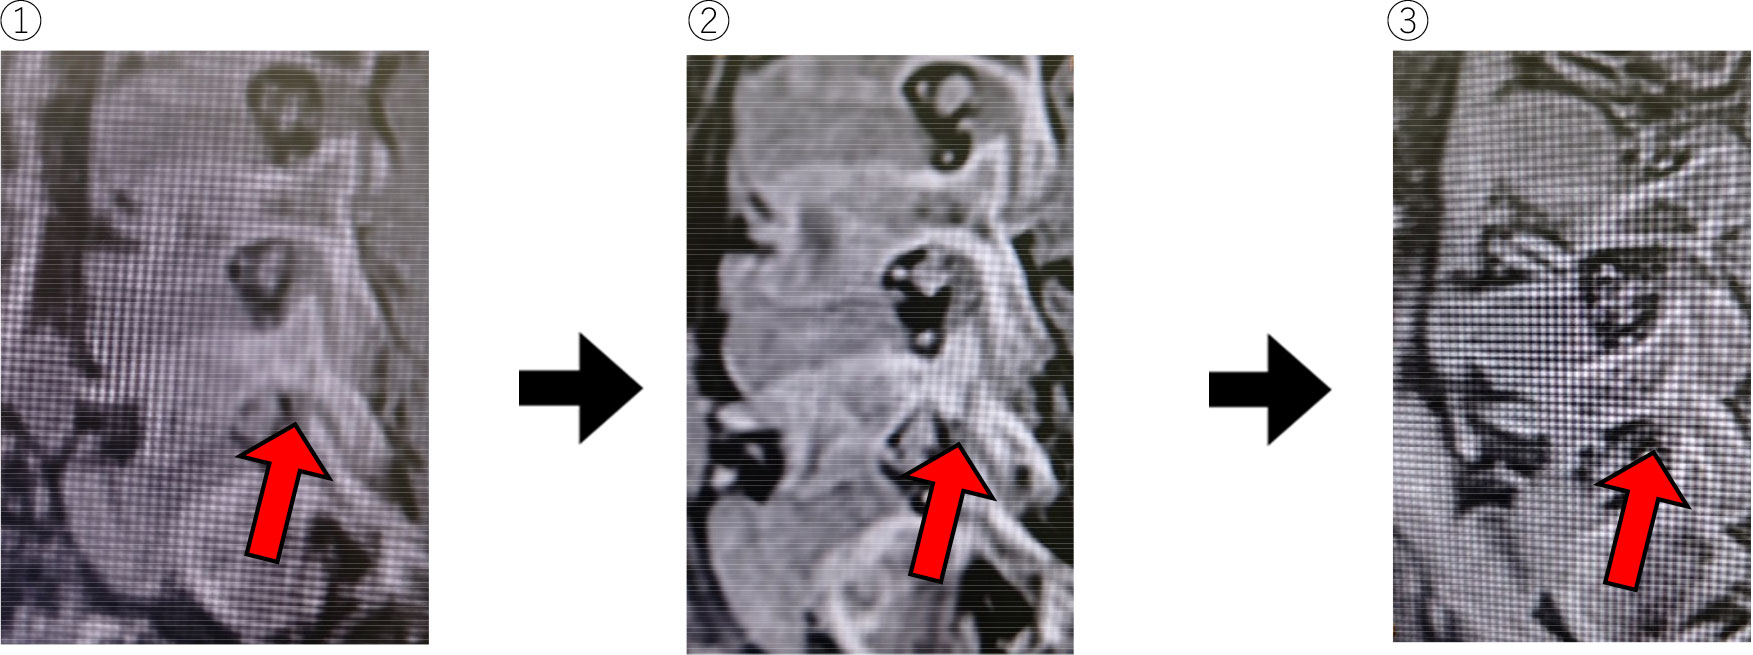

CTlike

- ①初期:骨折部を抽出している。

- ②1か月後:骨折部がかなりはっきりしているのがわかる。

- ③4か月後:骨癒合してきているのがわかる。